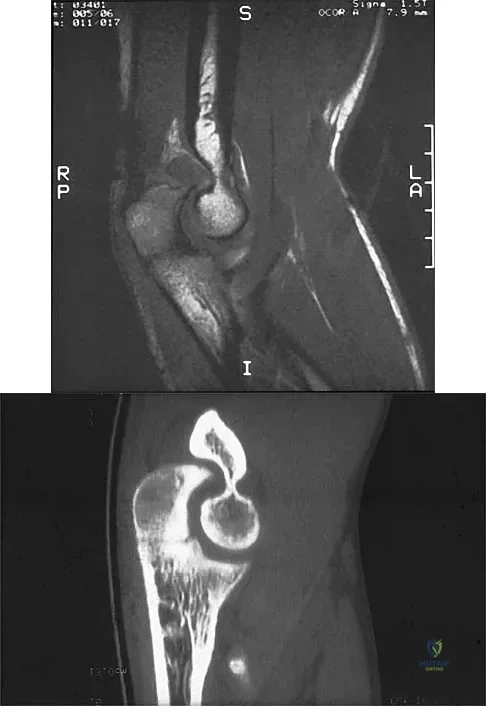

Question 15

A right-handed 20-year-old college baseball pitcher has had a 6-month history of vague right elbow pain while pitching. Examination reveals full flexion of the elbow and a loss of only a few degrees of full extension. The elbow is stable, but palpation reveals tenderness over the olecranon. Plain radiographs are inconclusive. MRI and CT scans are shown in Figures 20a and 20b. Management should consist of

Explanation